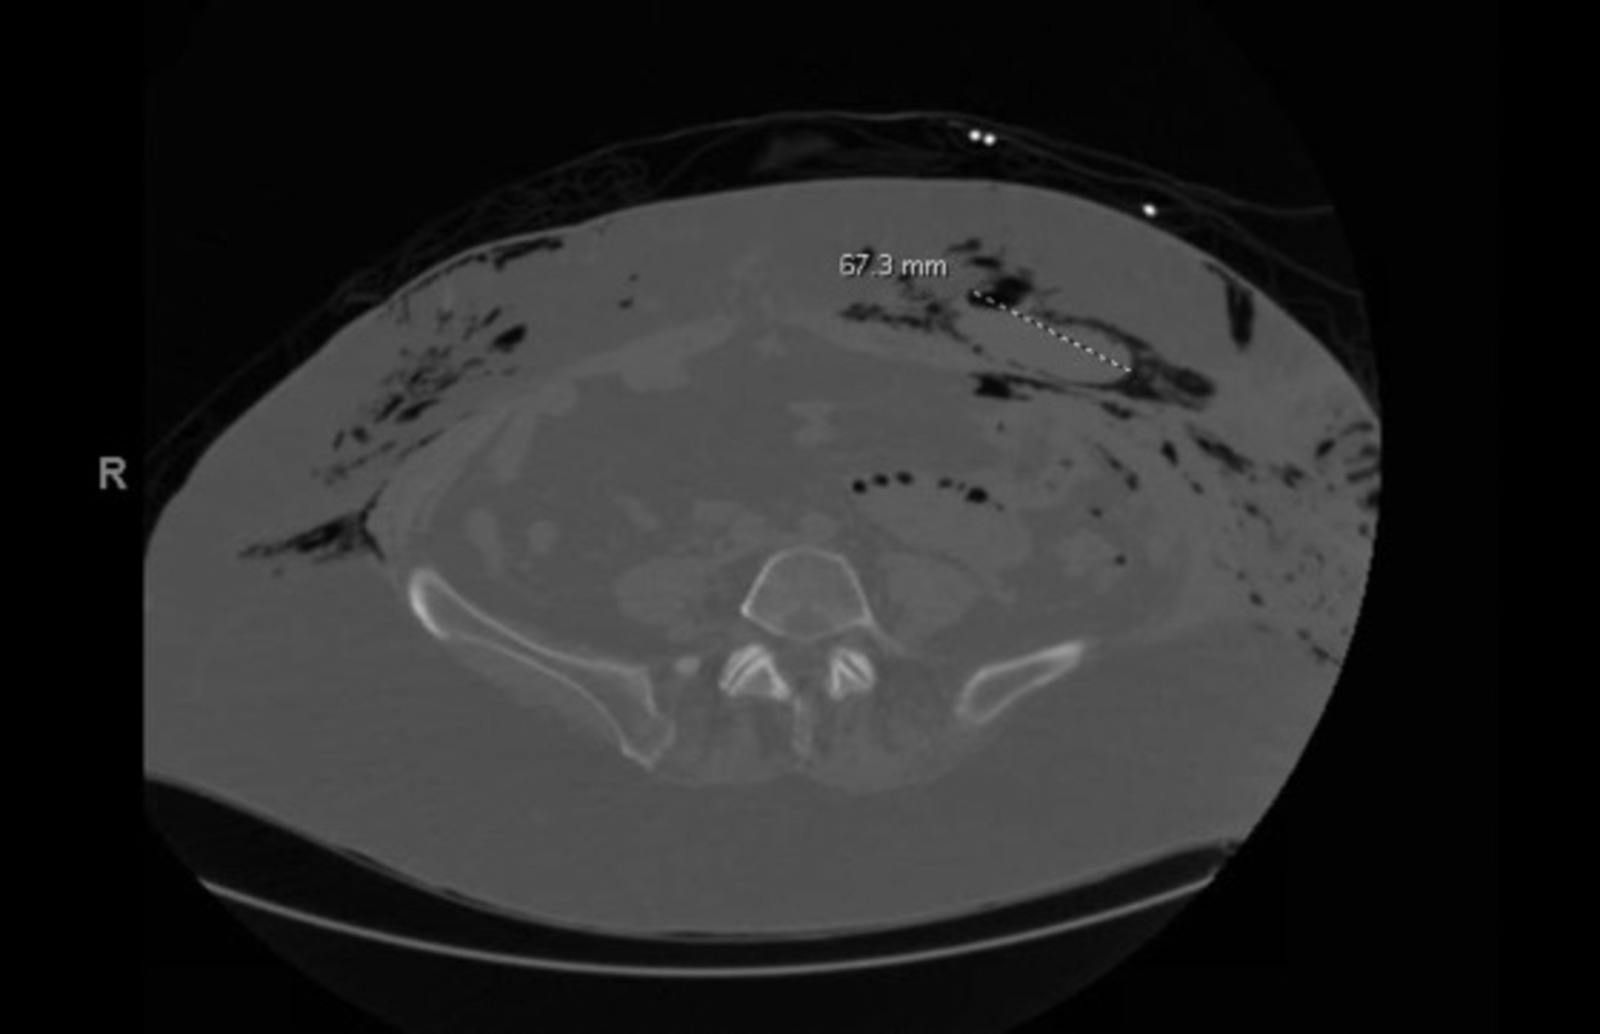

During the first day of her hospitalization, the patient underwent a computed tomography (CT) scan of the abdomen and pelvis which revealed a large pneumoperitoneum; soft tissue density in the anterior abdominal wall measuring 7.5 cm on the left, which may represent a hematoma; a stomach distended with fluid as well as fluid-filled loops of small bowel without definite transition zone, indicative of ileus; and gas within the small bowel wall, suggestive of bowel infection or trauma. The extensive subcutaneous and intramuscular air involving the abdominal wall extending up into the chest on CT raised concern for necrotizing fasciitis (Figure 2).